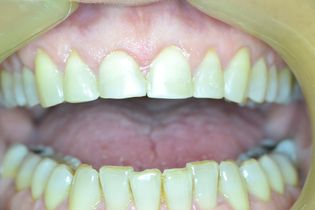

Η νεαρή αυτή ασθενής προσήλθε στο ιατρείο παραπονούμενη για την εμφάνιση των τεσσάρων άνω τομέων της.

Τα δόντια είχαν με την πάροδο των ετών σπάσει στην κοπτική τους επιφάνεια και το φαινόμενο αυτό επιδεινώνονταν σταδιακά με απώλεια όλο και περισσότερης οδοντικής ουσίας.

Αποφασίστηκε να αποκατασταθεί η δομική ακεραιότητα των δοντιών αυτών με χρήση σύνθετης ρητίνης νανουβριδικής τεχνολογίας (Herculite XVR Ultra/Kerr).

Η αποκατάσταση τους έγινε σε ένα ραντεβού και το αισθητικό αποτέλεσμα ικανοποίησε στο ακέραιο τις προσδοκίες της ασθενούς μας.